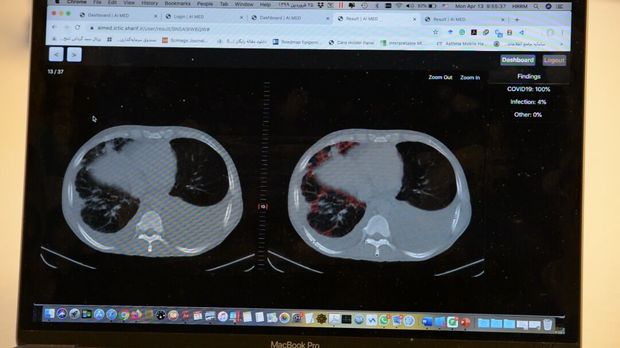

وی بیان کرد: کشور چین از هوش مصنوعی برای تشخیص این بیماری استفاده کرده است و یک شرکت برخاسته از دانشگاه استفورد آمریکا نیز فعالیت‌هایی را در این زمینه انجام داده است، ما نیز با تمرکز بر کاربرد هوش مصنوعی در سی تی اسکن، با نوآوری سامانه ای را برای تشخیص سریع و با دقت کووید ۱۹ طراحی کرده ایم که قابلیت تخمین حجم ناحیه عفونی را نیز دارد.

رییس گروه علم و فناوری اطلاعات و ارتباطات جایزه مصطفی(ص) همچنین افزود: سیستم‌هایی که در کشور چین یا آمریکا استفاده می‌شود، دقت بالای ۹۰ درصد دارند، نبوغ جوانان دانشمند ما، با پیش پردازش نوآورانه بر روی تصاویر سی‌تی اسکن و استفاده از راهکارهای توصیف پذیری در یادگیری ماشین، سامانه ای با دقت و حساسیت بالاتری را به وجود آورده است.

ربیعی گفت: سامانه ای که این تیم تحقیقاتی براساس هوش مصنوعی طراحی کرده است با نوآوری در پیش پردازش و پردازش تصاویر در شبکه‌های عمیق توصیف پذیر، به صورت پایدار و در زمانی کمتر از یک دقیقه، نتایج خوب و با دقت و حساسیت بالای ۹۷ درصد را به دست آورد. علاوه بر این سامانه حجم نواحی عفونی را نیز محاسبه می کند. این سامانه به طور رایگان در اختیار پزشکان و مراکز درمانی جهان قرار می‌گیرد تا با توجه به تعداد زیاد بیماران بتواند به پزشکان در تشخیص سریع و با دقت این بیماری کمک کند.

وی با بیان اینکه کوید ۱۹ در برخی از تصاویر در مراحل اولیه بیماری با چشم غیرقابل مشاهده است، اظهار کرد: از بیمارستان‌های مختلف، نمونه‌هایی را داشته‌ایم که امکان تشخیص این بیماری برای آن­ها از مشاهده تصاویر وجود نداشته است، اما سامانه هوشمند آی مد باتوجه به طراحی مناسب آن توانسته بیماری را در مراحل اولیه تشخیص دهد.